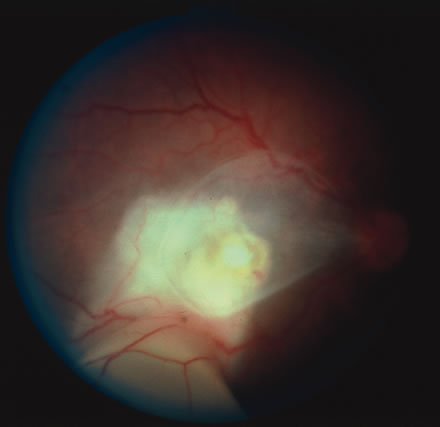

CMV retinitis is common in patients with AIDS. Perivascular granular white or yellowish infiltrates with hemorrhage are typical (Fig. 7). Minimal vitritis or anterior uveitis may be present. The posterior pole, including optic nerve, or peripheral retina may be involved. Optic neuritis may be retrobulbar. Resolution of retinal lesions reveals local retinal atrophy and pigment dispersion. Iridocyclitis may occur secondary to infection of ciliary processes. CMV retinitis in patients with AIDS is considered a poor prognostic sign in terms of life expectancy. Congenital CMV infection may also cause retinitis, as well as anterior uveitis, cataract, and optic atrophy. New foci of retinochoroiditis can develop in later years of congenital infection, and such infants require periodic reexamination as long as virus is shed in the urine.

Fig. 7. Cytomegalovirus retinitis in a patient with aquired immune deficiency syndrome (AIDS). Note the large area of retinal necrosis along with the perivascular distribution of the lesions.